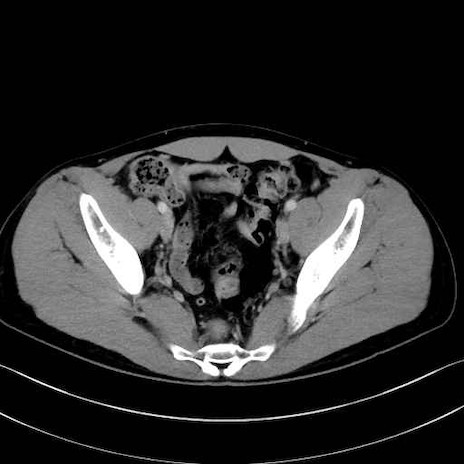

内閉鎖筋 (Obturator internus)

外閉鎖筋 (Obturator externus)